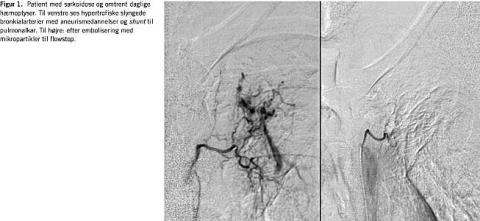

Litteratursøgning er foretaget primo august 2004 på MEDLINE/PubMed (hemoptysis AND intervention ). Artikler på engelsk, tysk eller skandinavisk er udvalgt med hovedvægt lagt på engelsksprogede publikationer fra de seneste ti år. Der er desuden foretaget håndsøgning i referencelisterne i de fundne artikler. Angiografiske billeder (Figur 1 og Figur 2 ) er fra egen afdeling til illustration af de berørte problemstillinger.

Alle systemiske arterier, som kan være bronkiale fødearterier, skal i princippet undersøges; primært bronkialarterier på den formodede blødende side, men også interkostalarterier, a. thoracica interna og andre grene fra a. subclavia og a. axillaris, såvel som a. phrenica inferior og a. gastrica sin. [3, 12, 15, 22, 23]. I princippet kan alle systemiske arterier i thorax indgå i den bronkiale cirkulation. De karakteristiske radiologiske fund i patologiske bronkialarterier, som kan ses ved bronkial angiografi er: 1) hypertrofiske og slyngede bronkialarterier, 2) områder med hypervaskularitet i lungen, 3) systemiske arterier til pulmonalarterier og/eller -vene-shunt , 4) bronkial-arterieaneurysmer og 5) kontrastekstravasation [24] (Figur 1). Disse fund er også til stede uden blødning, og det er en fordel at foretage embolisering elektivt, hvis der ikke foreligger akut massiv blødning. Op mod 33% af hæmoptysepatienterne har en nonbronkial systemisk arterie som blødningsårsag [3].